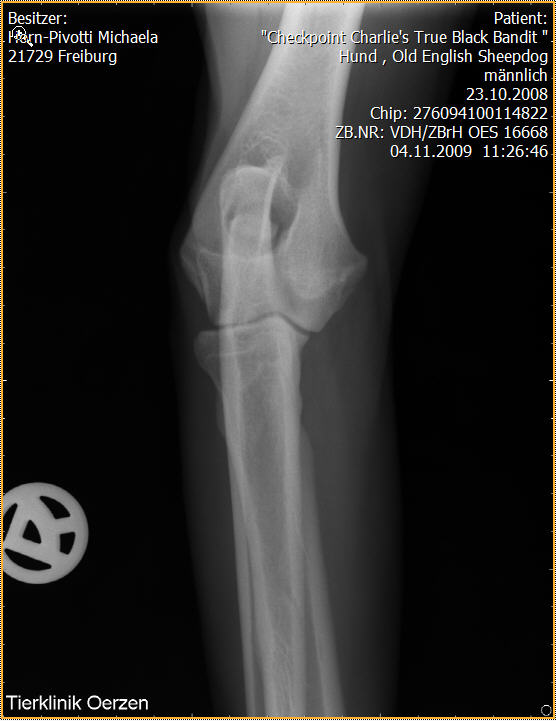

Röntgenaufnahmen HD/ED “Checkpoint Charlie’s True Black Bandit”